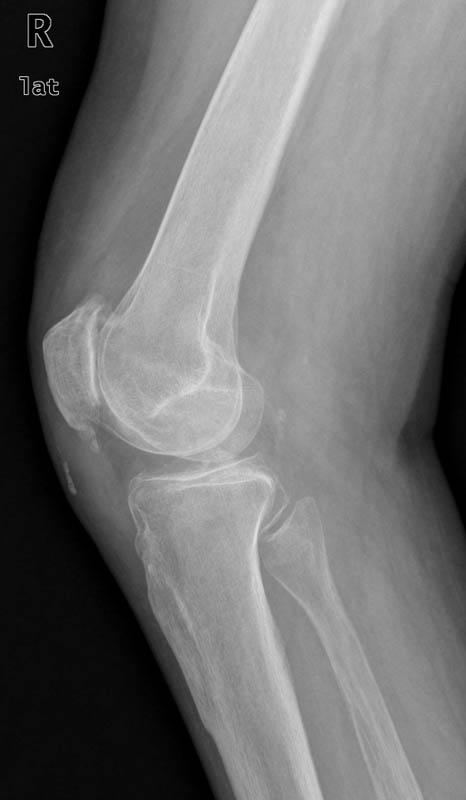

Prótesis completa de rodilla. Situación postquirúrgica. Lateral.

Prótesis completa de rodilla.Lateral.